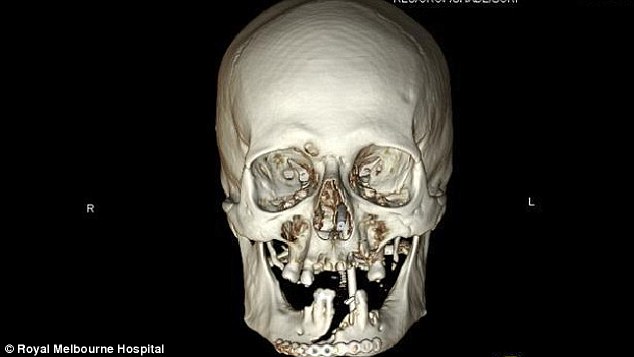

Le immagini ai raggi X del suo cranio mostrano l’enorme buco che si è procurato in faccia. Il signor Singleton è ora tornato a casa, visibilmente sfigurato, ma salvo. In futuro, ha detto, continuerà a lavorare con la motosega.